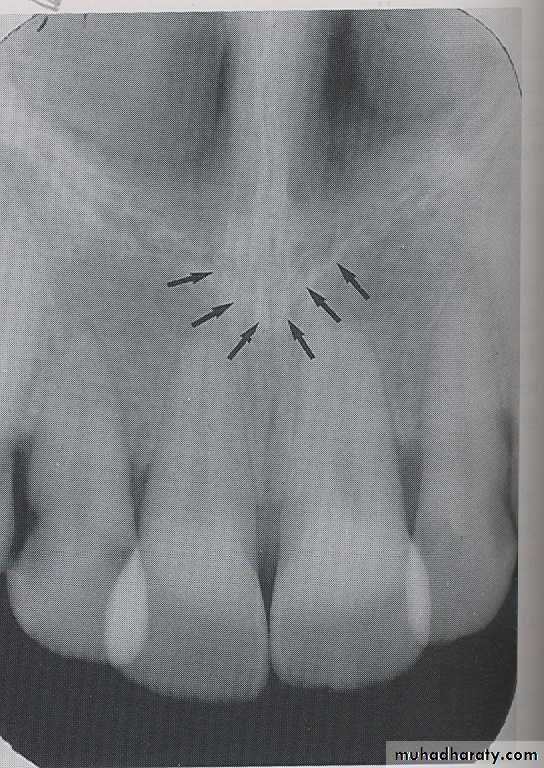

Radiographs of the region of the mandibular symphysis in infants demonstrate a radiolucent line through the midline of the jaw between the images of the forming deciduous central incisors. This suture usually fuses by the end of the first year of life, after which it is no longer radiographically apparent.GENIAL TUBERCLES

The genial tubercle are tiny bumps of bone that serve as the attachment sites for the genioglossus and geniohyoid muscles, its located on lingual aspect of the mandible. On mandible periapical radiograph the genial tubercle appears as a ring shaped radiopacity below the apices of the mandibular incisor.

LINGUAL FORAMEN

The lingual foramen is a tiny opening or hole in the bone located on the internal surface of mandible, its located near the midline and surrounded by genial tubercle. Radiographically, the lingual foramen appears as small radiolucent dot located inferior to the apices of mandibular incisor.